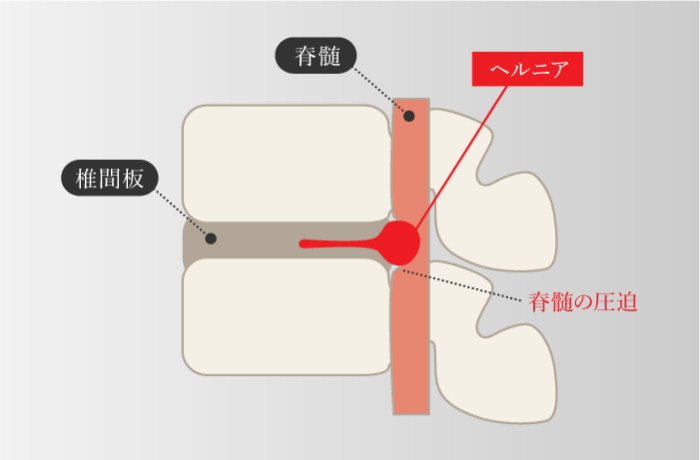

頸椎ヘルニア

-

椎骨間にある髄核が飛び出し、脊髄や神経根を圧迫して痛みなどが生じる

頸部椎間板症

-

髄核がずれ、線維輪に亀裂が入る痛みが生じ、その状態が続くことによって徐々に椎間板の水分が減少して変性を起こし、機能が低下する